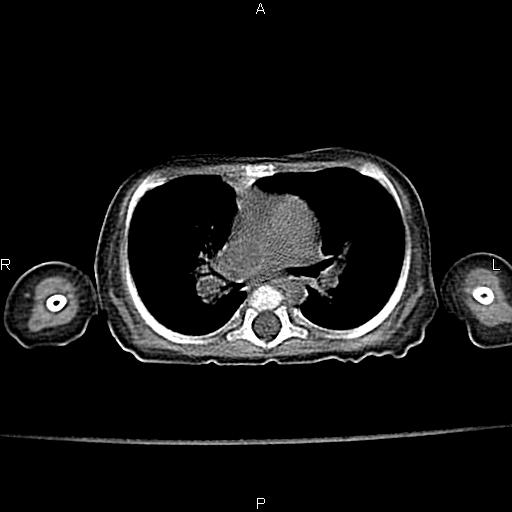

以下是引用aa13877358820在2010-7-26 12:35:00的发言:[br]男性,三个月,卧位胸片,咳嗽、气促、发热14天,两肺闻及细小水泡音。[br]

以下是引用jsdtd在2010-7-26 14:42:00的发言:[br]胸腺呈帆状,体位所致,没事。